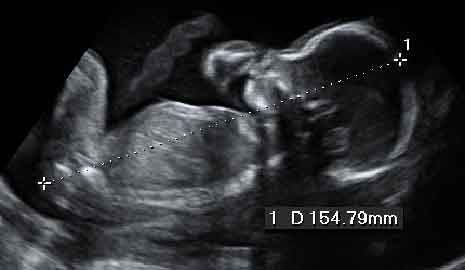

Niña bostezando

Cara de perfil con la boca abriéndose: se aprecia parte del brazo y el cordón umbilical.